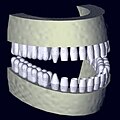

- die Digitale Volumentomografie (DVT).

Rekonstruiertes 3D-Zahnmodel aus Daten eines DVT-Scans -